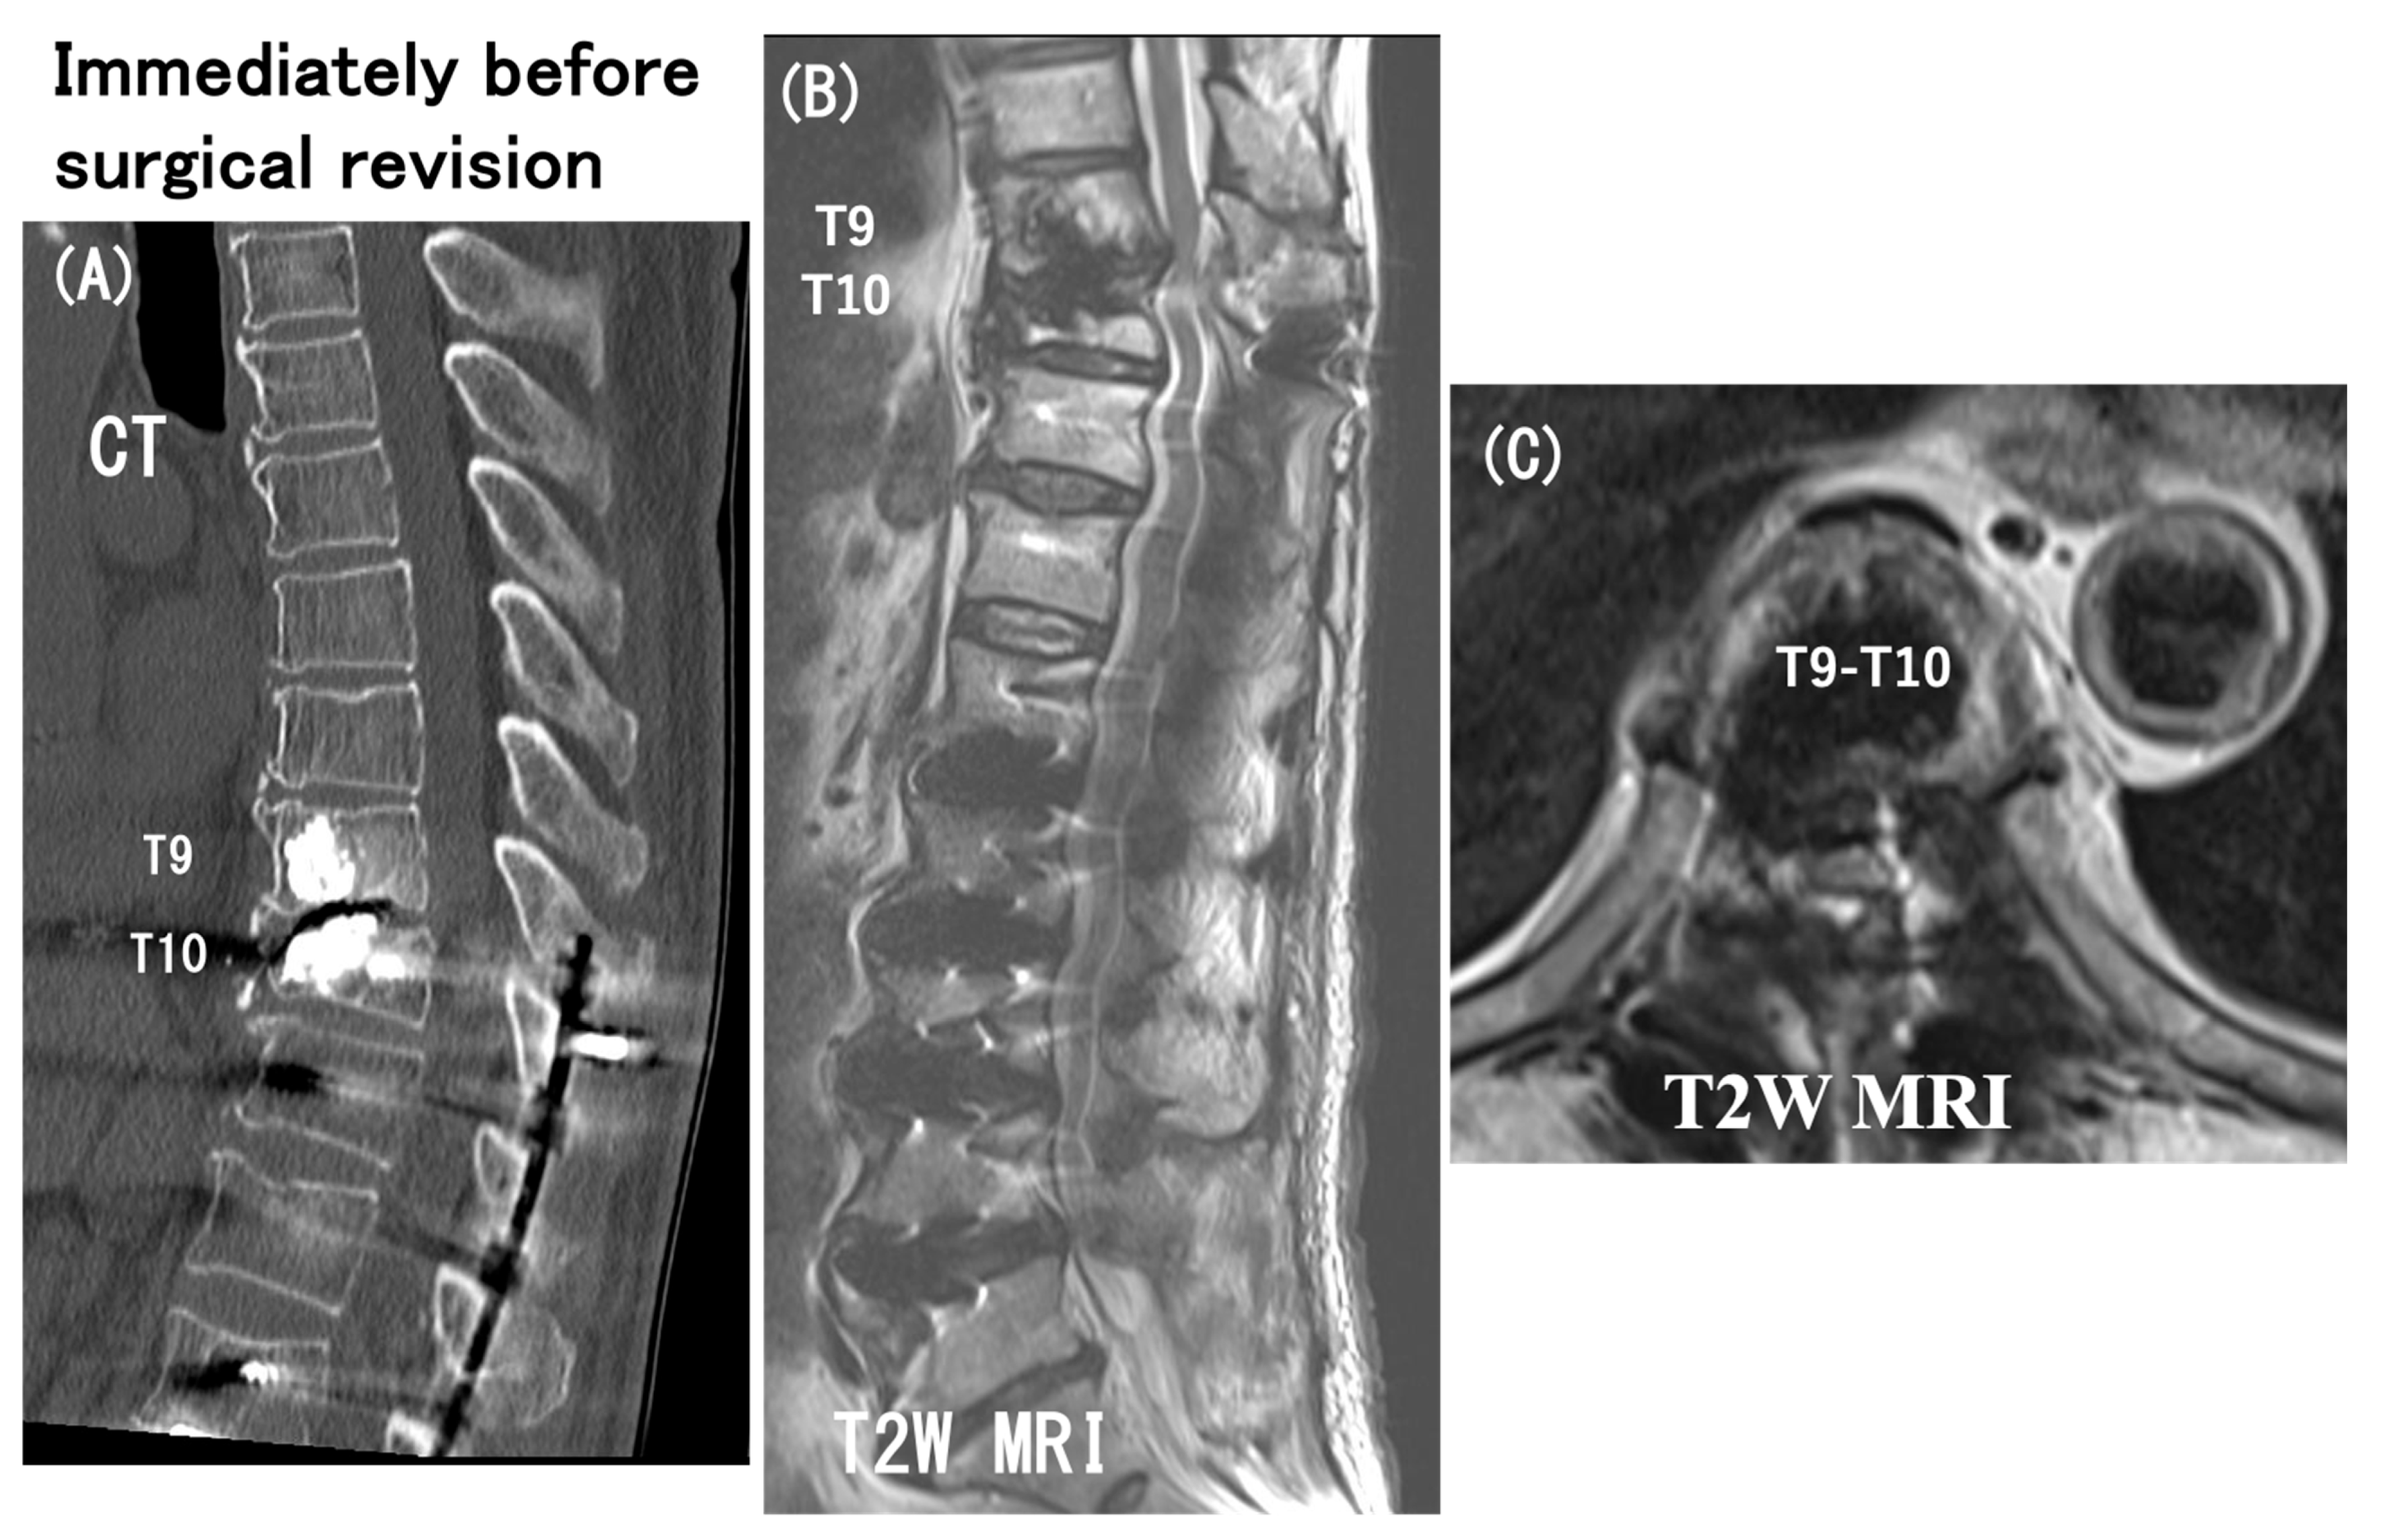

3.6. Case Presentation

- Case no. 6

- 2.

- Case no. 4